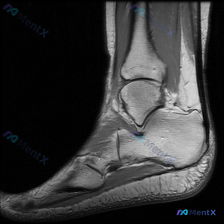

看到这个有意思的病例,整理了完整的分析思路分享给大家。 病例核心影像信息 这是一张踝关节MRI矢状位T1加权图像,原始疑问是观察到「软组织液体」,系统影像评估结果如下: 1. 骨性结构:各骨皮质连续,无骨折、骨质破坏,骨髓信号均匀,关节对位正常,关节面光滑,无明显骨赘或软骨下囊肿 2. 韧带肌腱:跟...